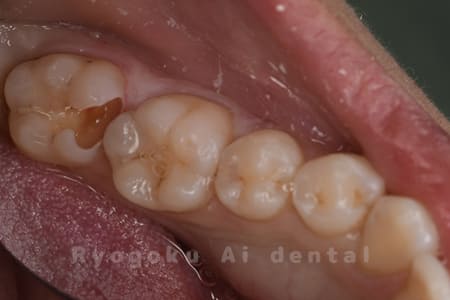

Case08

-

- 原因

- 虫歯

- 治療内容

- セラミックインレー

- 治療費用

- 77,000円

奥歯の黒い点が気になるということで来院された患者さんです。白い詰め物を外したところ、虫歯が中で大きく広がっていたため、患者さんと相談し、セラミックインレーで治療を行いました。

<リスク・副作用>

過度の咬合や衝撃で割れることがあります。